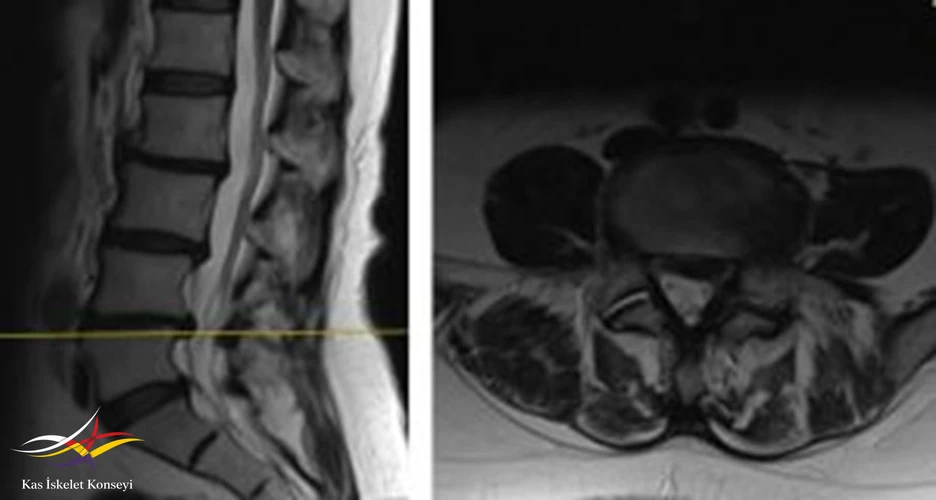

İncelemeler: Lomber MRG: L4-5 diskal bulging ve sol foraminal stenoz var. Kalça MRG istendi, iki yanlı trokanterik bursit rapor edildi.

Resim 1. Lomber MRG, L4-5 seviyesi median kesit.